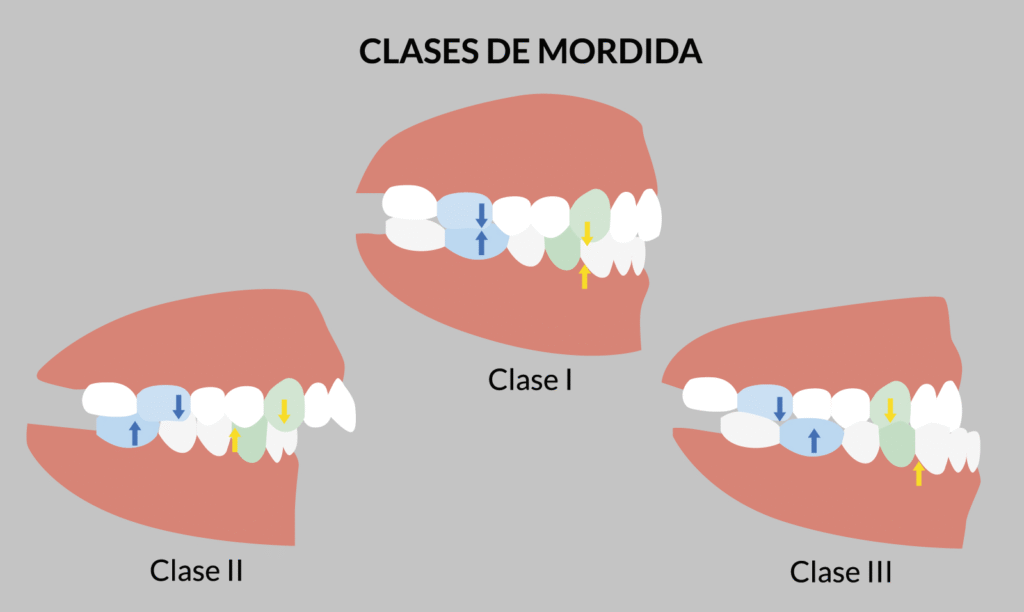

Detectar y tratar las maloclusiones a tiempo evita que se agraven con el crecimiento. Un aparato de ortopedia dental puede corregir mordidas cruzadas, abiertas o profundas, antes de que comprometan la función y estética.

La ortopedia dental infantil es una herramienta preventiva y correctiva fundamental para garantizar un desarrollo bucal saludable. Si notas que tu hijo presenta problemas de mordida, hábitos orales como chuparse el dedo, alguna clase de tela ó dificultades al morder y hablar, acudir pronto a una valoración con un especialista puede marcar una gran diferencia.